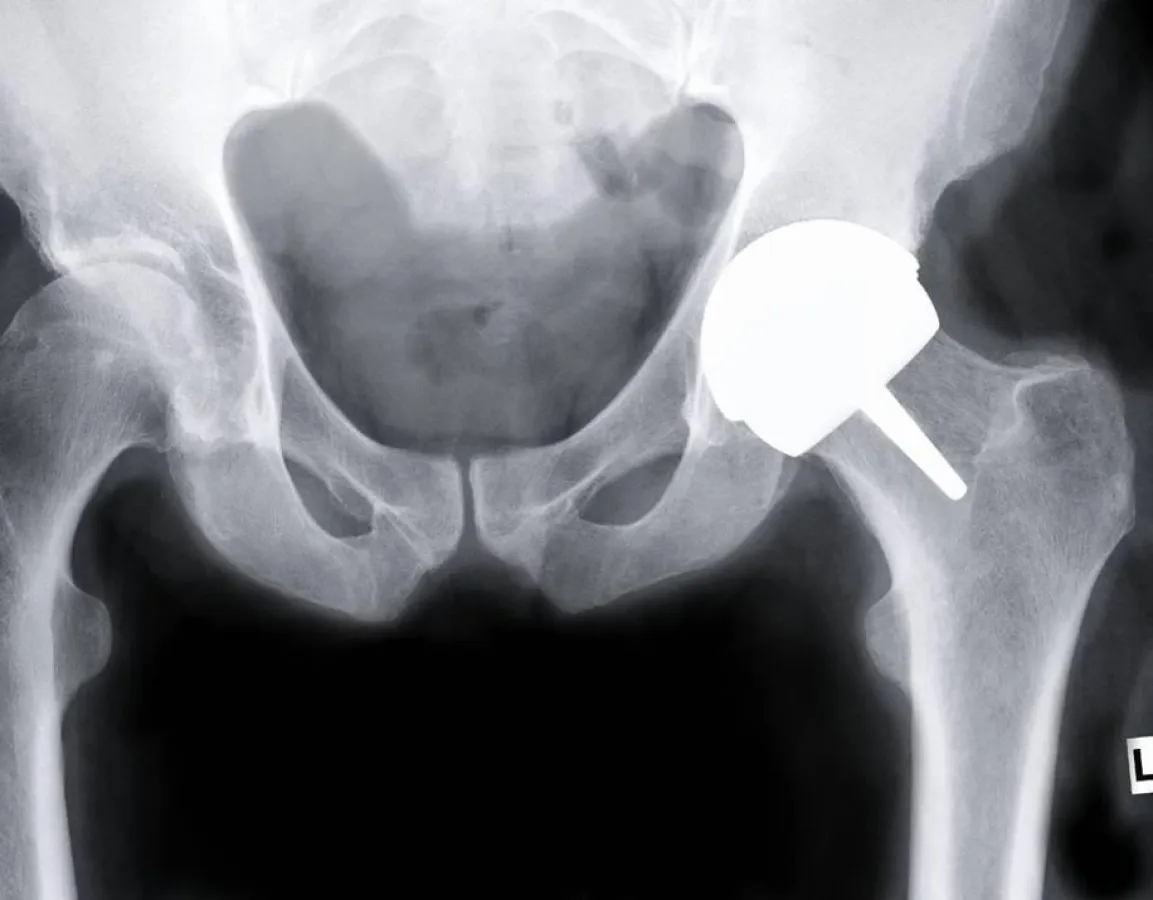

Der Gelenkersatz zählt heute zu den häufigsten

und auch erfolgreichsten Operationsverfahren.

Dennoch werden die Operateure immer wieder vor therapeutische

Herausforderungen gestellt. Sei es beispielsweise bei der

Versorgung der wachsenden Zahl junger, aktiver Menschen,

die einen Gelenkersatz benötigen oder bei Patienten mit

Metallallergien, für die spezielle Implantate zur Verfügung

gestellt werden müssen. Die Erfahrungen der letzten Jahre

zeigen, dass für die unterschiedlichen Patientengruppen mit

ihren individuellen Bedürfnissen auch besondere operative

Verfahren und Implantatkonzepte angeboten werden sollten.

Minimal-invasive Hüftendoprothetik –

Versorgung der Zukunft?

Jan-Hauke Jens